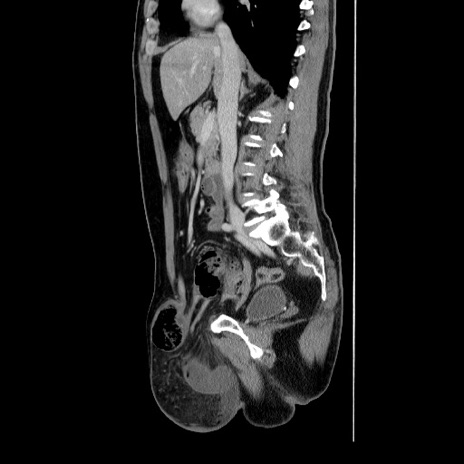

症例34(矢状断像)

【症例】60歳代 男性

【主訴】右鼠径部膨隆

【現病歴】1年程前より右鼠径部膨隆あり。自己にて還納可能だったため放置していた。3時間前より右鼠径部の脱出を認め、還納困難となり受診。

【身体所見】右鼠径部に小児頭大の膨隆あり。弾性硬であり、用手還納は困難。左鼠径部にも膨隆を認める。脱出はなし。